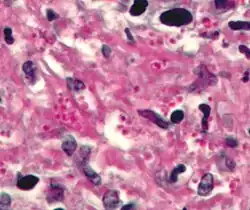

[13]Periodic acid-Schiff is a histology special stain used to mark carbohydrates (glycogen, glycoprotein, proteoglycans). PAS is commonly used on liver tissue where glycogen deposits are made which is done in efforts to distinguish different types of glycogen storage diseases. PAS is important because it can detect glycogen granules found in tumors of the ovaries and pancreas of the endocrine system, as well as in the bladder and kidneys of the renal system. Basement membranes can also show up in a PAS stain and can be important when diagnosing renal disease. Due to the high volume of carbohydrates within the cell wall of hyphae and yeast forms of fungi, the Periodic acid -Schiff stain can help locate these species inside tissue samples of the human body.